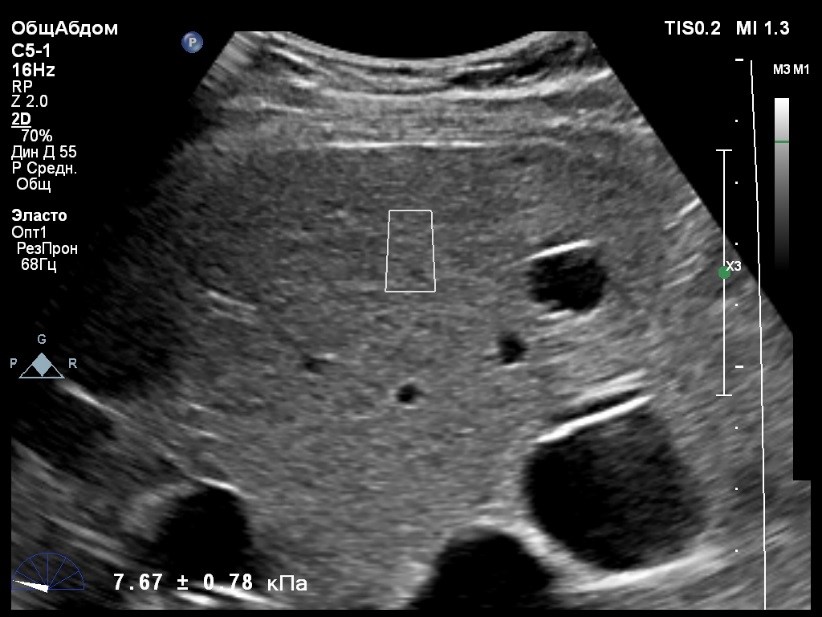

Пациент обратился к доктору с направлением на исследование степени жесткости печени в июне 2017 года. Из истории болезни, пациент страдает Гепатитом С с 2015 года. Лечение не получал. В апреле 2016 года, с помощью транзиентной эластографии была установлена медиана жесткости печени 5,8 kPA (4,4-7,7). На момент настоящего исследования, пациент не принимал пищу на протяжении 4 часов, АСТ, АЛТ не превышают патологических значений. Для оценки жесткости была выбрана технология компании Philips ElastPQ (точечная эластография) и прибор компании Philips Epiq 7 Исследование было проведено в соответствии с клиническими рекомендациями для ультразвуковых приборов компании Philips. В результате исследования были получены следующие результаты:

| 1 [4.94] kPa | 2 [7.09] kPa | 3 [7.13] kPa |

| 4 [4.74] kPa | 5 [5.17] kPa | 6 [7.78] kPa |

| 7 [6.19] kPa | 8 [7.63] kPa | 9 [4.64] kPa |

| 10 [6.18] kPa | 11 [4.49] kPa | 12 [4.54] kPa |

| 13 [6.08] kPa | | |

Стандартное Отклонение [1.17] kPa Медиана Жесткости [6.08] kPa Фактор Качества IQR/Med 9%

Зона интереса расположена на более чем на один сантиметр глубже капсулы, параллельно ходу луча, в середине изображения, в участке печени лишенном артефактов.

Капсула видна как белая линия перпендикулярная ходу ультразвукового луча, исследования производятся приблизительно в одном и том же сегменте печени.

Для интерпретации полученных клинических данных были использованы Рекомендации по проведению эластографии сдвиговой волной для оценки жесткости печени при использовании ультразвуковых аппаратов компании Филипс с примером протокола. Анамнез основного заболевания пациента достаточно короткий и показатели жесткости печени, полученные в 2016 свидетельствуют об отсутствии значимых фиброзных изменений. Однако, в течении всего времени пациент не получал специфического лечения. Данный факт является показанием для динамического наблюдения и оценки жесткости печени. Подготовка пациента соответствовала проводимому исследованию. Представленные слайды проведенного исследования свидетельствуют о правильном техническом исполнении проб, что позволяет заключиться о достоверности полученных измерений. Таким образом, учитывая полученную медиану жесткости на уровне 6.08 кРа (4.49 – 7.78 kPa) и уровень стандартных отклонений не превышающих 30%, полагаю, что уровень степени фиброза соответствует стадии F 0-1. Заведующий отделением УЗД МЦ «Асклепий», Глушенко Д. Е.